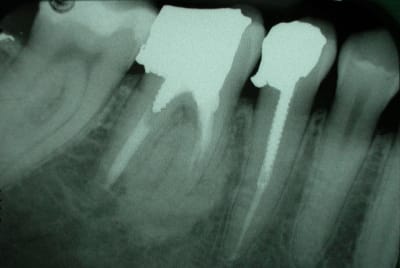

qu'est que cela peut il etre?

dent asymptomatique.

Normal mon chou, rien à faire lésion cemento-osseuse très difficile à classer même pour l'oms

tu peux écarter les fibromes cemento-ossifiant (il manque le halo radio clair périphérique) e n'est pas non plus une dysplasie fibreuse il n'y apas de déplacement de structure dentaire tu peux t'orienter vers une dysplasie céménto-osseuse péri apicale à forme dense quel age? Femme?

c'est^pas méchant, c'est souvent une formation cementoïde corrélable au traitement endo, l'os est fou et ne reconnaît plus les cellules cimentaire...

mais si j'avais souhaité reprendre le traitement avant de realiser une couronne, y a moyen? ou vaut mieux laisser tomber.

je ne suis pas endo, mais en temps qu'osseuphile je ne rettt pas pas d'inflammation sup dans ce flou ossifiant et les images en distal de la 7 c'est là depuis longtemps ou c'est de l'amalgame tout frais, fais ta couronne en expliquant la présence de cette image ostéocondensante à la patiente , femme 3 décade correspond bien avec une dysplasie cemento-osseuse terme anapath qui veut dire on s’en fout il ya des cellules cementaire et osseuses en structure malformative résultant d'une anomalie du développement d'un tissu .

pour le bout d'amalgame figée en distale de 47, je ne sais pas depuis quand il est là car c la première fois que je vois la patiente.

dernière interrogation, ce phenomene est il associé à une resorption radiculaire?(qui pourrait comprometre la durée de vie de la dent?)

tres lentement evolutif certe!